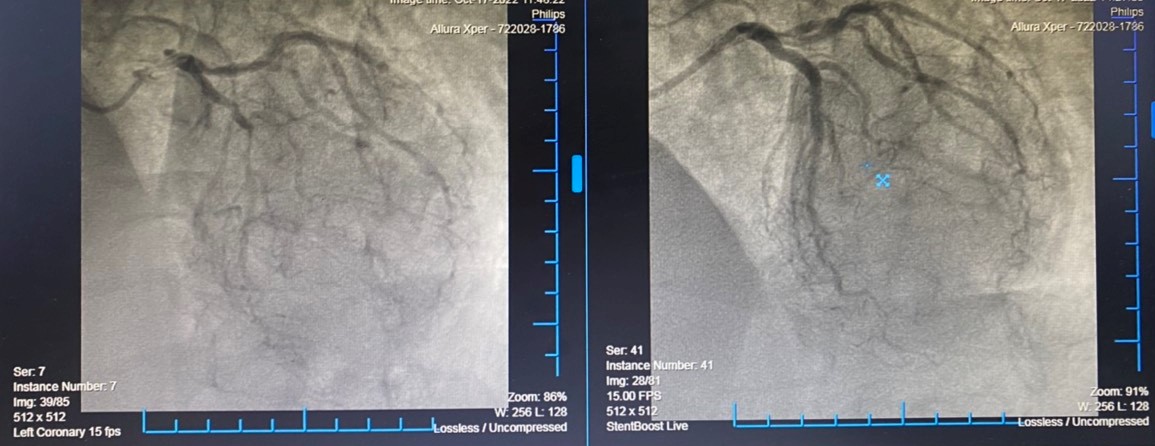

Kết quả chụp mạch vành của bệnh nhân phát hiện Tổn thương rất nặng toàn bộ hệ động mạch vành: Hẹp khít lỗ vào thân chung động mạch vành bên trái, hẹp khít đoạn 2 động mạch liên thất trước, tắc hoàn toàn mạn tính Stent cũ động mạch vành bên phải, có tuần hoàn bàng hệ một phần từ bên trái sang.

Sau khi đã hội chẩn và thống nhất các phương án điều trị, xác định thủ phạm chính gây nhồi máu cơ tim cấp lần này là Động mạch vành bên trái vị trí thân chung và hẹp khít LAD2, bệnh nhân được can thiệp đặt 2 Stent LM – LAD2. Ekip can thiệp đã rất thận trọng, tiến hành mở thông hoàn toàn thân chung động mạch vành trái, đặt 2 stent thành công. Quá trình can thiệp thuận lợi, sau can thiệp, bệnh nhân đã hết đau ngực, khó thở và hồi phục tốt.